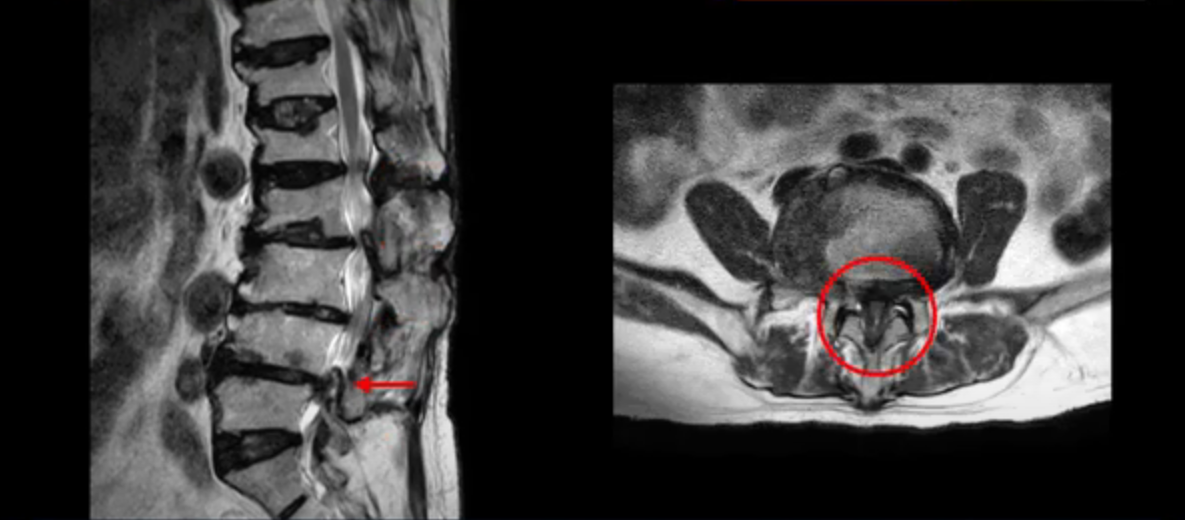

이 환자분은 허리 여러 마디가 다 안 좋아서 오랫동안 허리가 아프셨고 허리도 일찌감치 굽으셨습니다. MRI를 보시면 허리 여러 마디가 심하게 안 좋습니다.

보시다시피 4번 5번 마디에는 심한 중심성 협착이 있고

1번 2번,

2번 3번,

3번 4번에도 중심성 협착이 있습니다.

또 신경 가지가 빠져나가는 추간공도 좁아져 있습니다. 이런 이유로 환자분의 다리가 저리고 아픈 겁니다.

또한 척추뼈 여러 개가 압박 골절과 변형으로 찌그러져 있고

골다공증도 심하시고 보시다시피 근육량이 너무 적습니다. 근육이 정상적인 분들과 비교해보면 근육이 얼마나 적은지 알 수 있습니다.